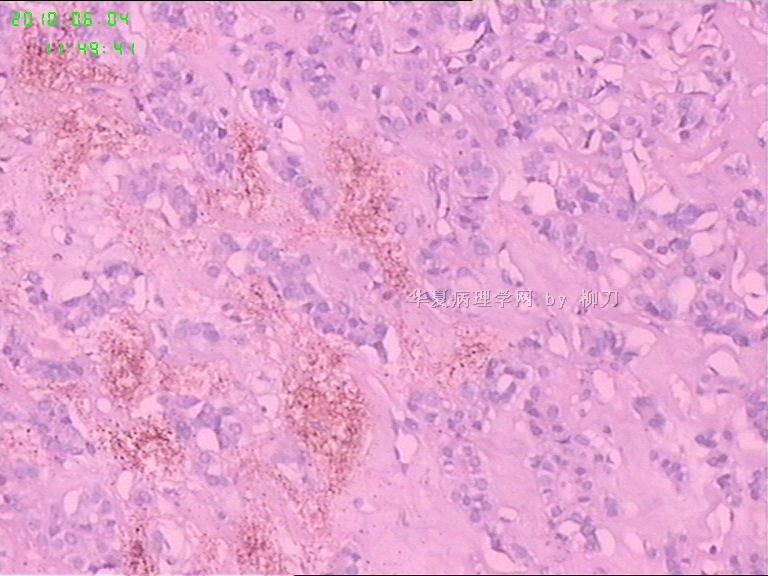

灰白结节2枚,其一2.5x1.8x1.5cm,包膜完整,内为褐色胶质,其二3x2.5x1.5cm包膜完整,切面灰白实性。附件镜下为后者。

可能楼主看到那些核的变化吧?但是没有其他支持的条件,还是应该是结甲。

就这几幅图似乎不够说明问题,细胞有一定的异型性,但是,最好能采到交界处的情况再判断。癌与非癌,最好能有组织结构与细胞异型性结合来看。

有些核透明,无其它特点,恶性证据是没有。